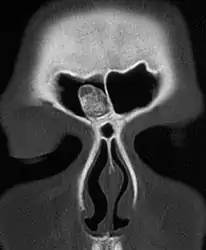

CT scan showing an osteoma growing on inside of skull bone

Medical imaging such as X-ray, CT scan and MRI show dense, clearly defined, round white tumors attached to bone.[1] They can be left alone if not troubling, and surgically cut out if pressure symptoms.[1] The surgery may be possible through the nose, without making a large cut.[3]

Medical imaging such as X-ray, CT scan and MRI show dense, clearly defined, round white tumors attached to bone.[1] They may be diagnosed when having medical imaging for another reason.[3] Osteomas of the paranasal sinuses and skull base can be diagnosed using CT-scan without intravenous contrast, allowing its size and relation to nearby important structures to be assessed.[3] A biopsy is not usually required.[3]